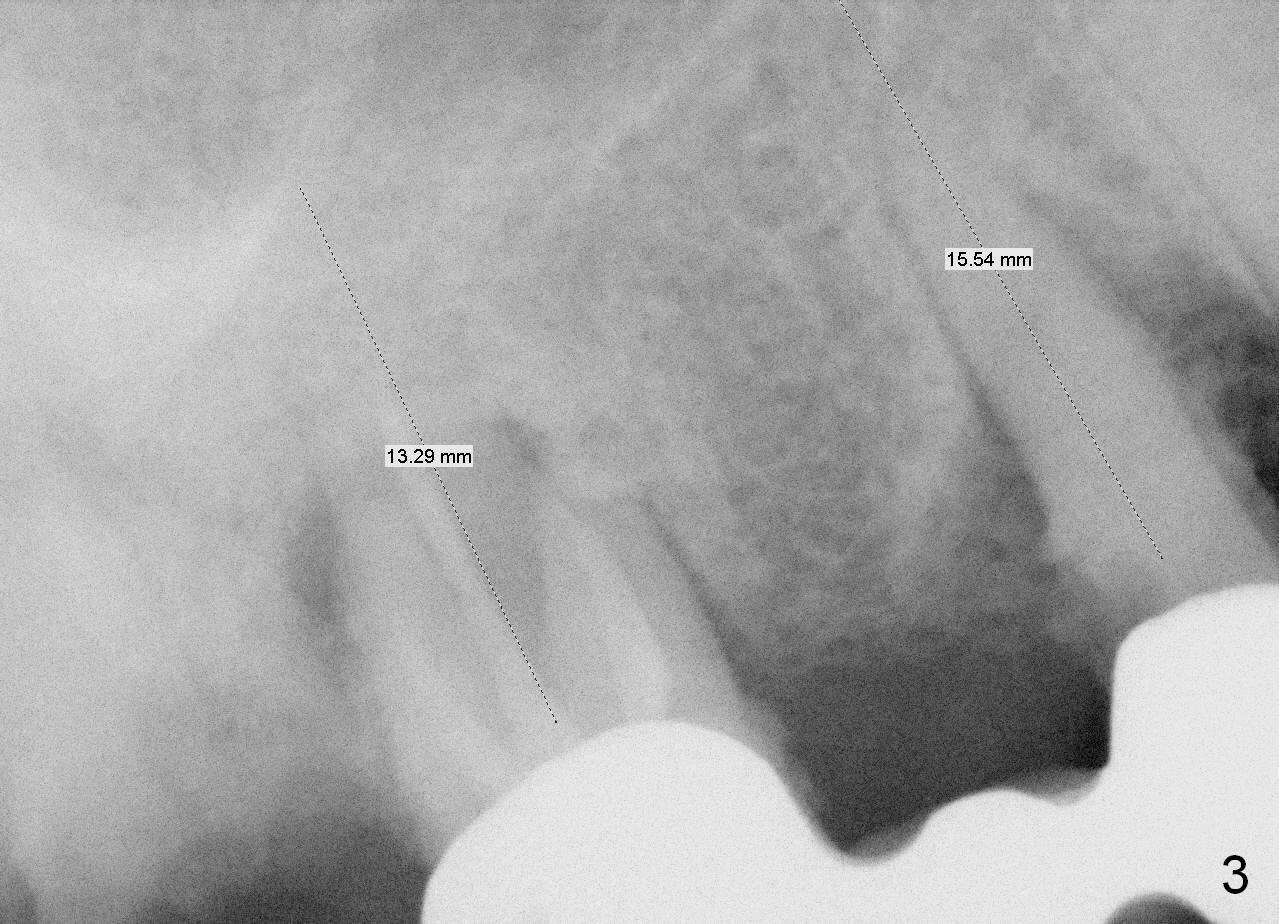

A 78-year-old lady (YT) has had poor dentition.  The tooth #2 fractured 3 years ago (Fig.1).  Now bone loss around the abutments for the bridge at #3-5 is more severe (Fig.2).  There is an abscess palatal to the tooth #5.  After extraction, the socket at #3 should be large (treated with 2% Xylocaine/1:50,000 Epinephrine).  An extra wide implant is expected.  Since there is more than 12 mm of bone in height (Fig.3), a UF implant is the most appropriate (6, 6.5 or 7x12 mm, Fig.4).  The longest extra wide SM implant is 10 mm.